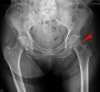

X-ray : 대퇴경 골절(Femoral neck fracture)